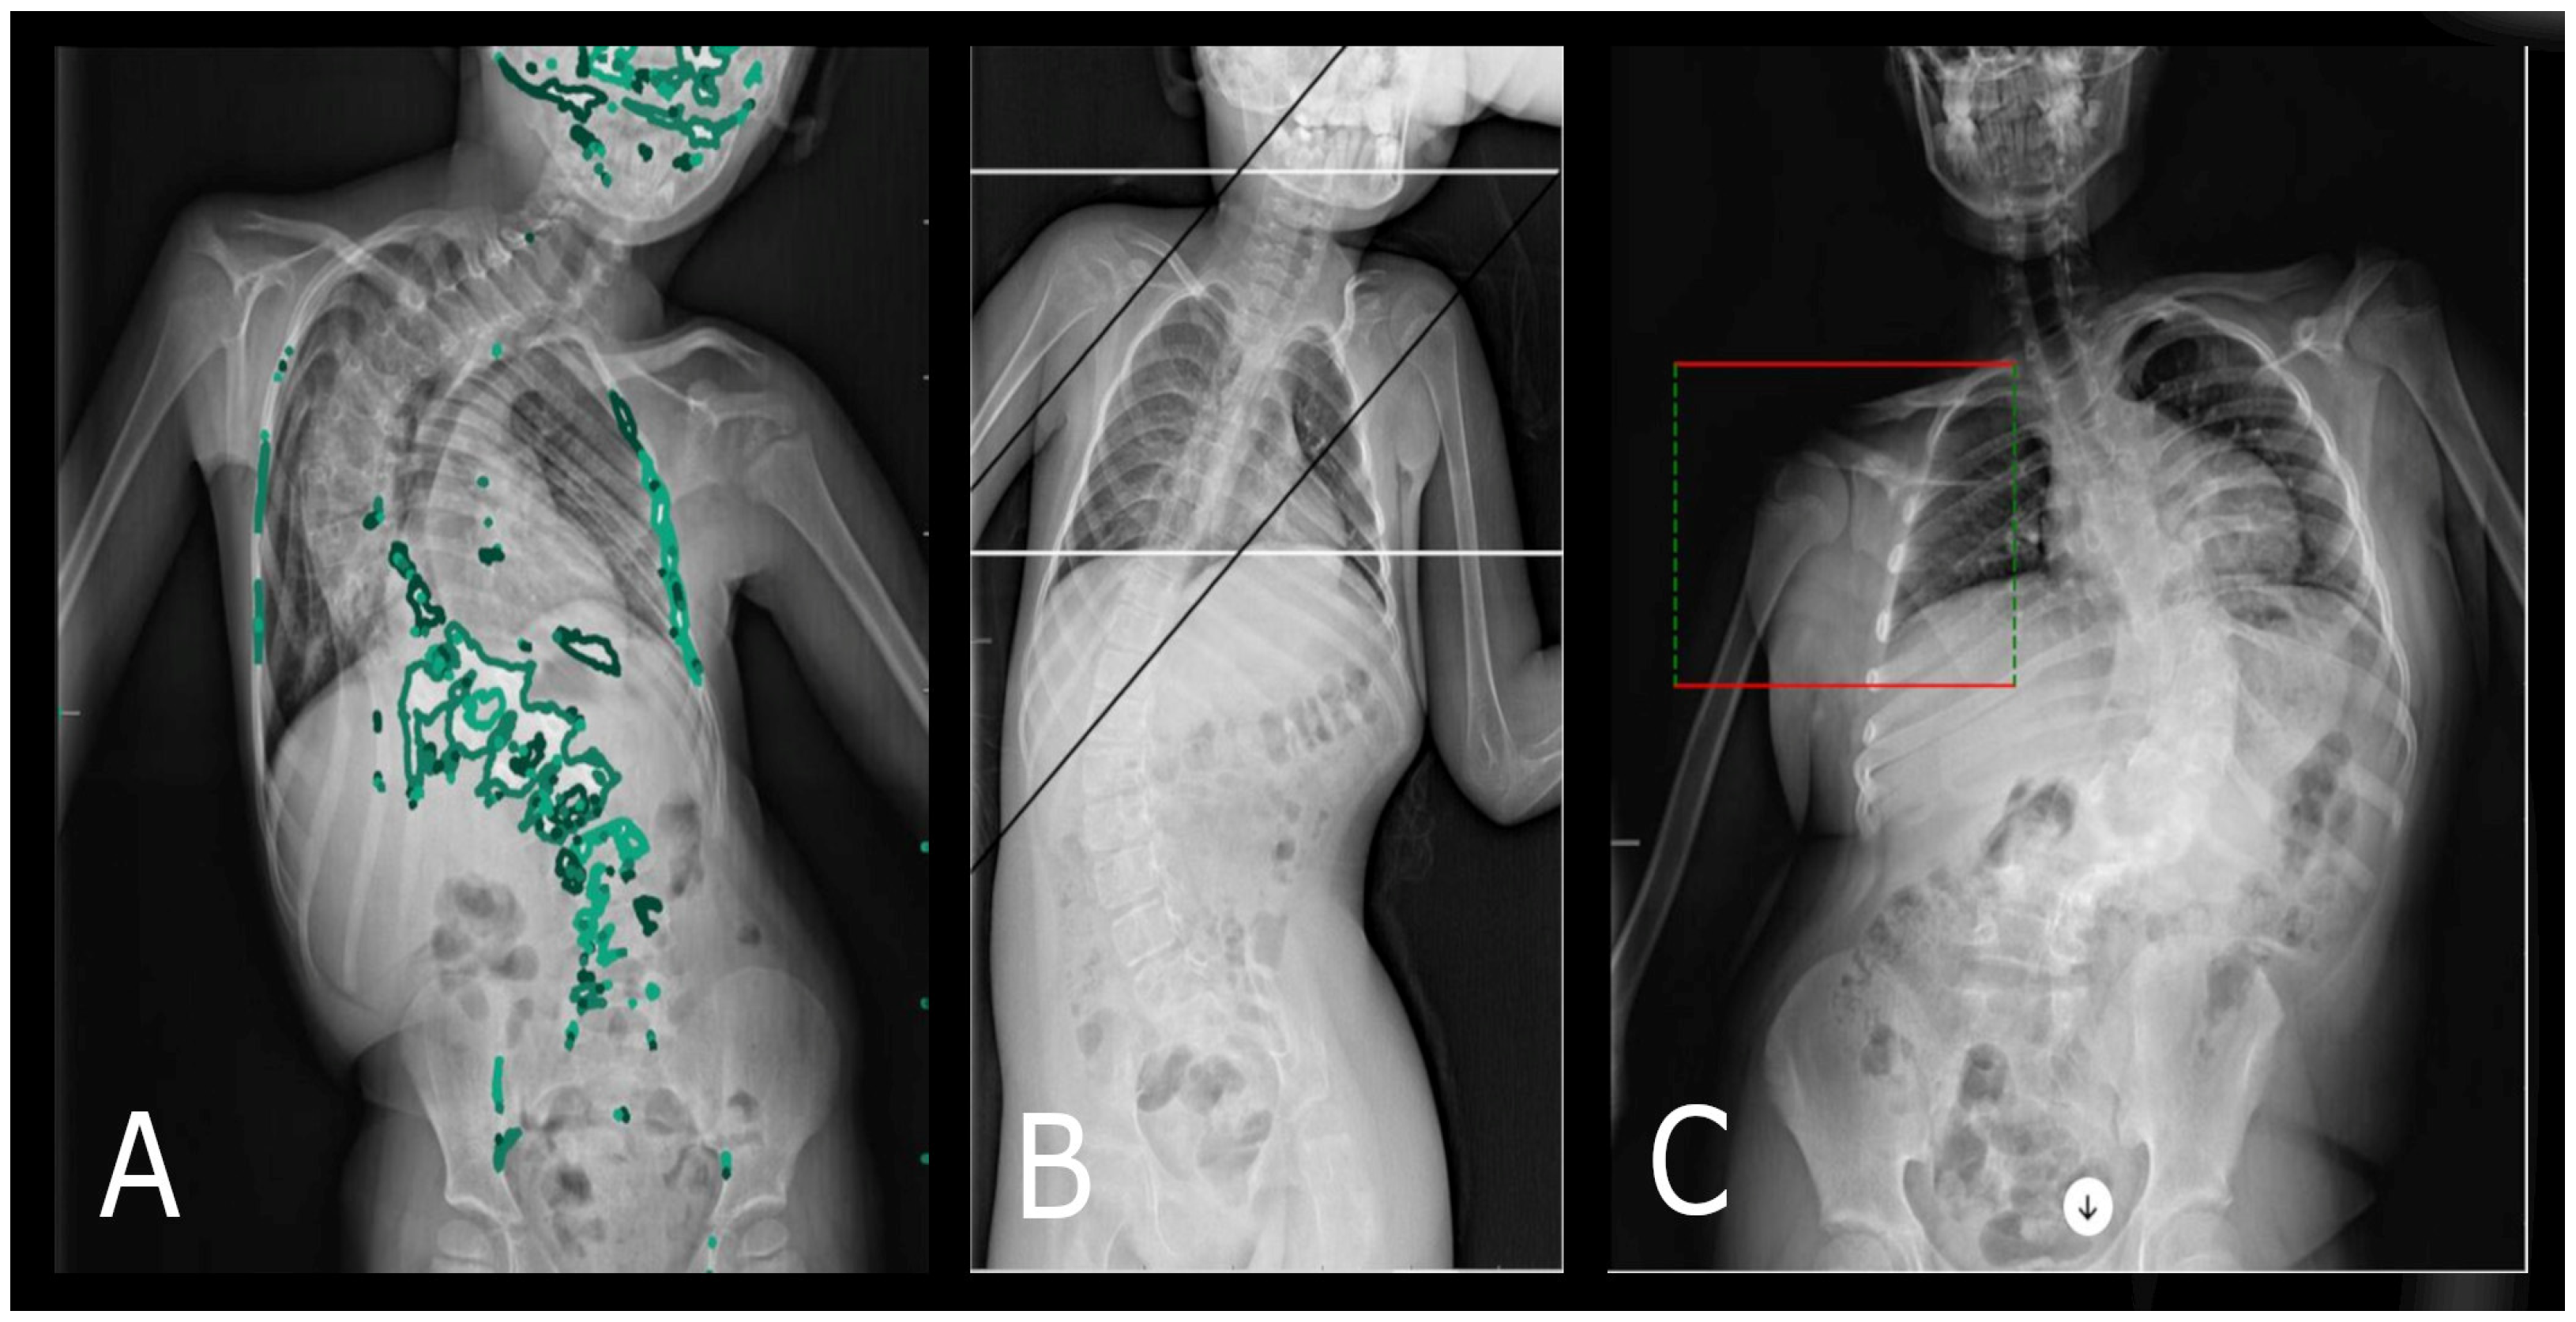

Scoliosis classification is highly diverse, considering various criteria such as the curvature angle, patient age, etiology, deformation location, direction of deformation, and the number of curvatures. For the purposes of this work, we simplify scoliosis into categories: single-curve (resembling the shape of the letter ‘C’) and double-curve (resembling the shape of the letter ‘S’, also called ‘S’-shaped scoliosis) [26]. The severity of scoliosis is determined based on the curvature size, measured using the Cobb method, with severe scoliosis defined as a deformation where the curvature angle exceeds 40 degrees [27] (Figure 1).

Figure 1. (A) Posturographic AP projection X-ray showing severe left-sided single-curve scoliosis with a Cobb angle of approximately 75 degrees measured between L4/L5 and Th6/Th7. (B) Posturographic AP projection X-ray showing severe right-sided single-curve scoliosis with a Cobb angle of approximately 86 degrees measured between L4/L5 and Th7/Th8.